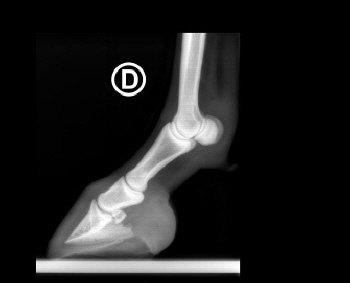

Röntgenbilder akuter- und chronischer Hufrehehufe vorher und nachher

Nachstehend stellen wir einige Röntgenbilder von Hufrehepferden ins Netz, welche das Vorher und das Nachher zeigen. Wir möchten damit aufzeigen, dass durch eine richtige Hufbearbeitung ein Hufbein wieder in eine korrekte Lage innerhalb der Hornkapsel zu liegen kommen kann.

In besonders schweren Fällen wurde doch zumindest eine Optimierung angestrebt.

nachher